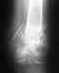

Здравствуйте уважаемые специалисты. Мне 28 лет у меня чрезвертельный перелом с смещением

три месяца назад сделали операцию поставили пластину (монотонная конструкция с шеячно-дифазарным углом в 145 градусов) все заживает вроде нормально но в результате у меня нога короче на 4-4,5 см пластину обещали снять в сентябре т е через год могу ли я сделать в вашем институте операцию по удлинению конечности тазобедренной кости и возможно ли это сделать одновременно в тот момент когда пластину будут снимать то есть за одну операцию Хотел бы записаться на консультацию к вашему травматологу напишите пожалуйста что для этого надо какие документы и снимки и если надо я сделаю дополнительные снимки

Покажите снимок, хотя бы последний. Можно здесь. Можно приехать на Московскую, 12, с понедельника по четверг включительно, с утра.